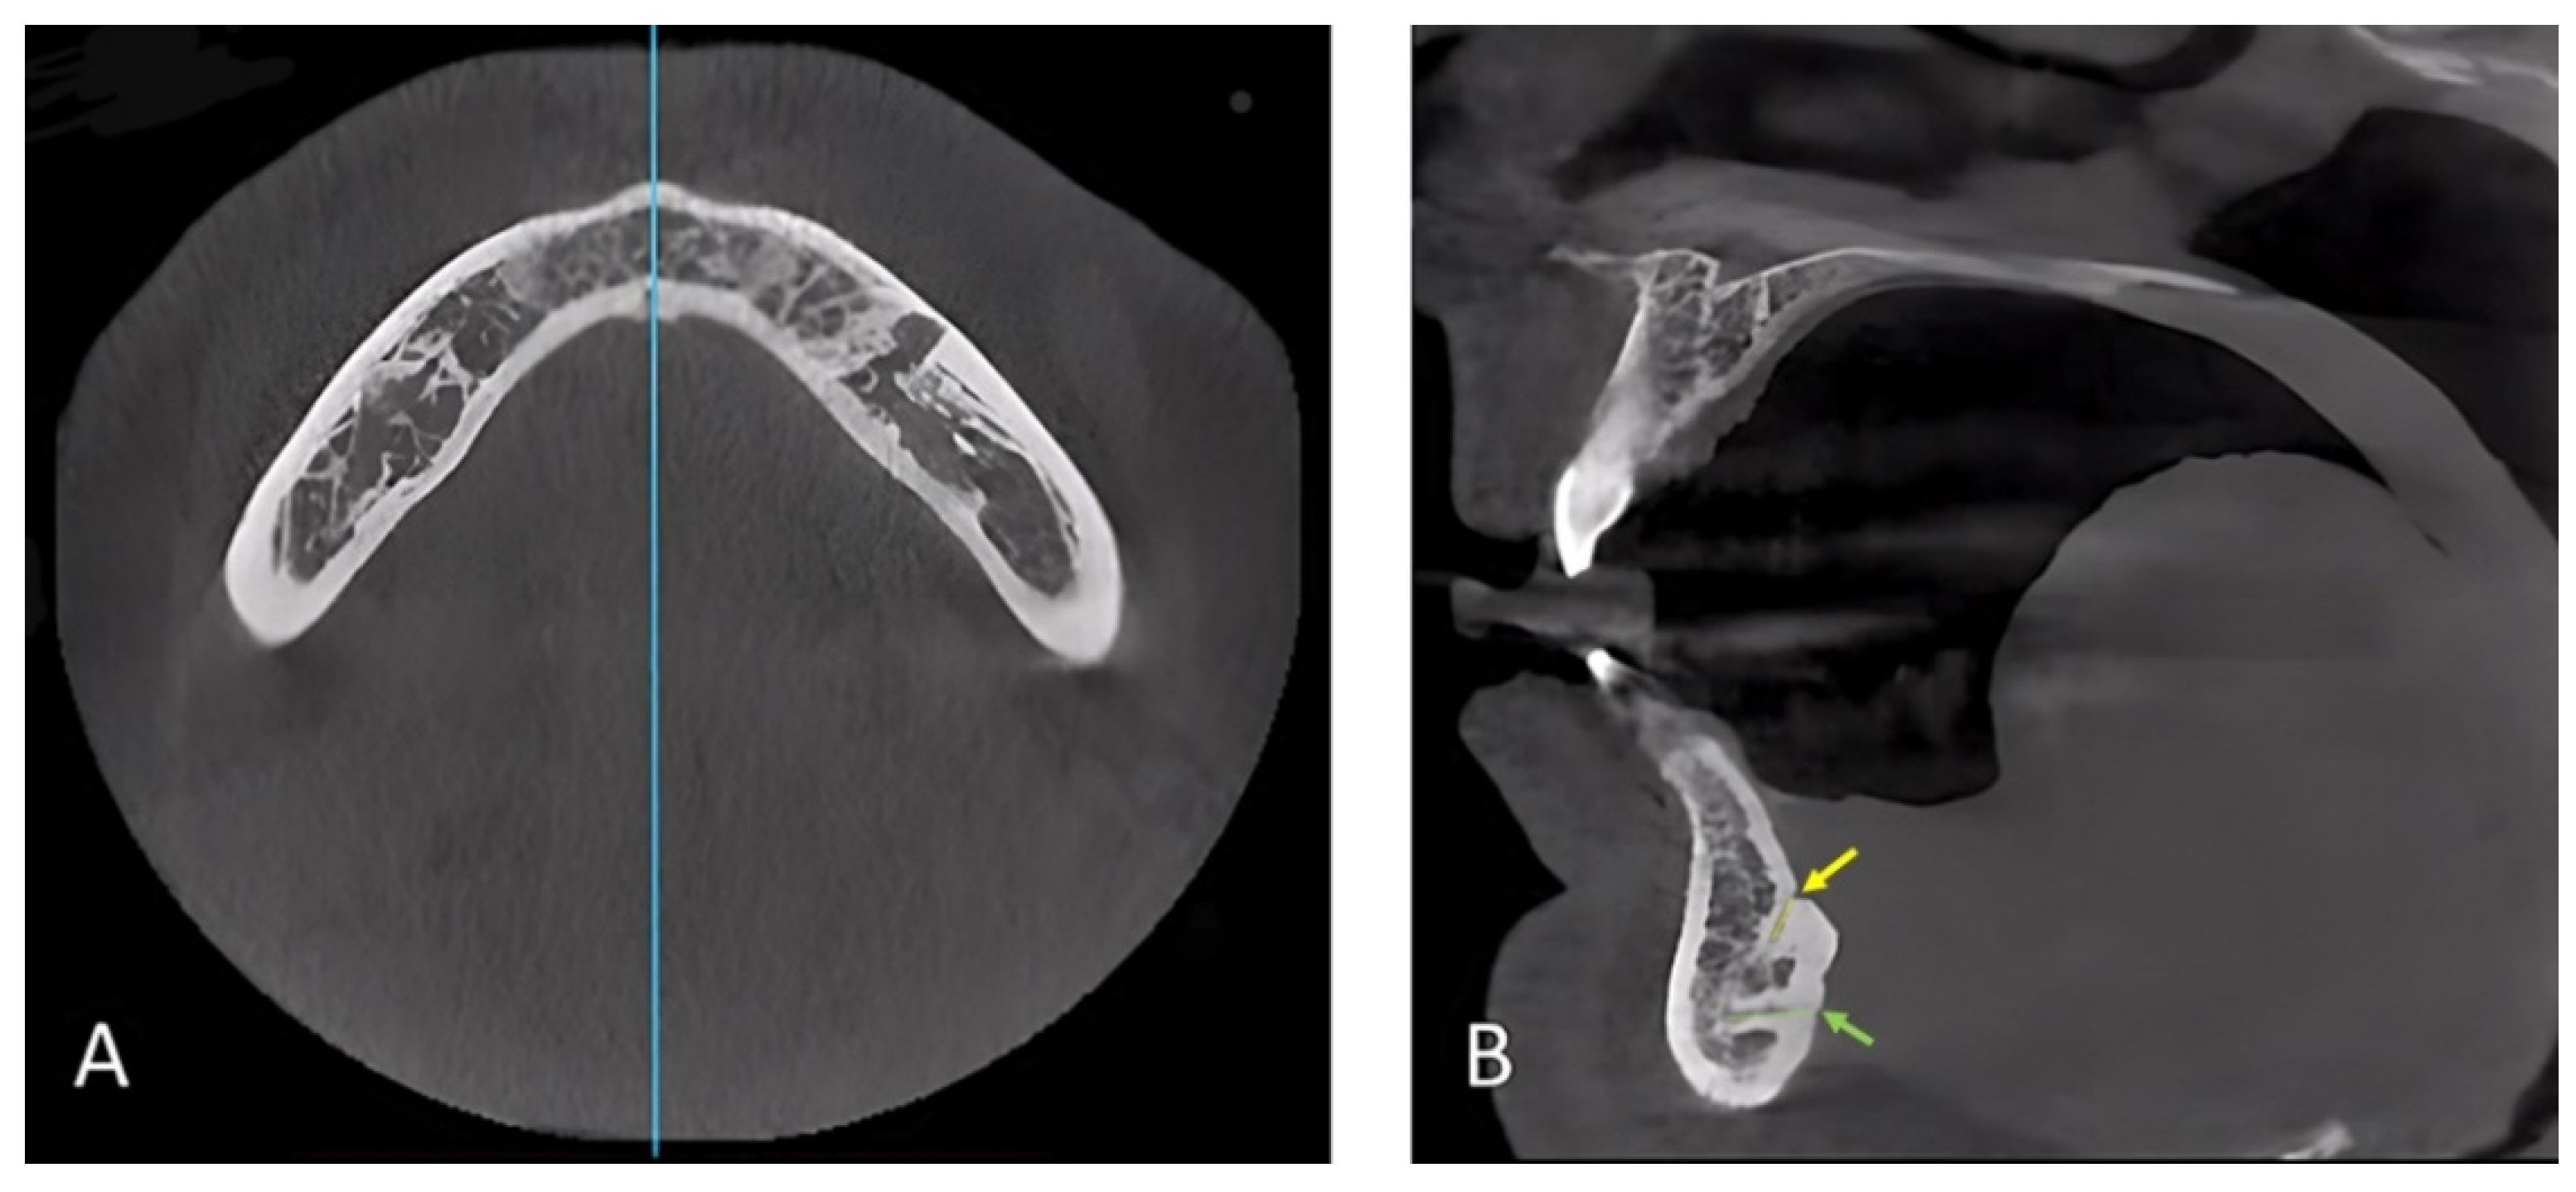

2.2. Data Collection, Image Reconstruction, and Assessments